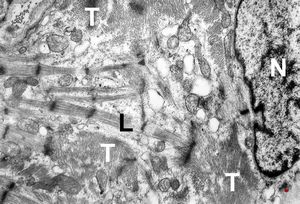

M,47y. | hypertrophic cardiomyopathy - left ventricle ( N - nucleus, T- transversally oriented, L- longitudinally oriented myofibrils )